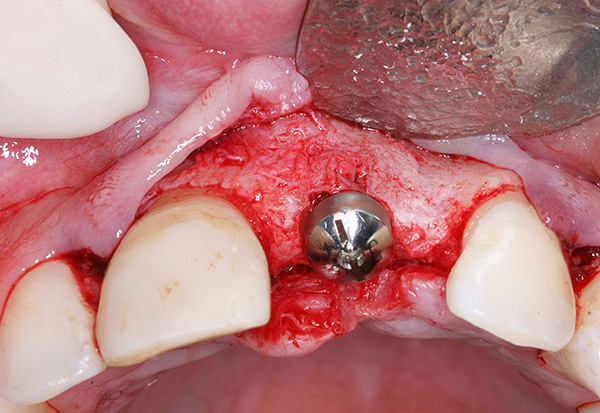

As fotos abaixo mostram os implantes removidos:

Após a remoção do implante móvel, é realizada uma preparação complexa do poço para a próxima implantação, que pode ser realizada após 1-2 meses. Por exemplo, com uma diminuição significativa no tecido ósseo ou na proximidade do seio maxilar, pode ser necessário construir o osso da mandíbula sob o implante dentário (operação de elevação do seio).